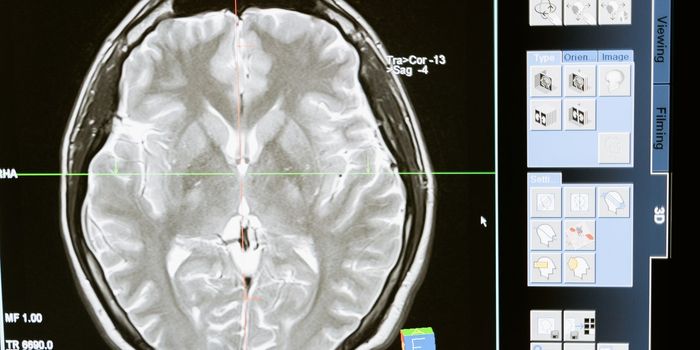

SEP 01, 2016Clinical & Molecular DXThe beloved actor Gene Wilder died earlier this week from complications of Alzheimer’s disease. He was one of the ...

JUN 27, 2016Genetics & GenomicsAlmost 80,000 people die each year worldwide due to brain inflammation diseases, and it’s hard to know how many of ...

MAY 11, 2016ImmunologyThe brain’s immune system potentially could be harnessed to help clear amyloid plaques, which are a hallmark of Al ...

JUL 25, 2016Genetics & GenomicsThe immune cells of the brain are to thank for clearing Alzheimer’s disease-related plaques. Mutations in a certai ...